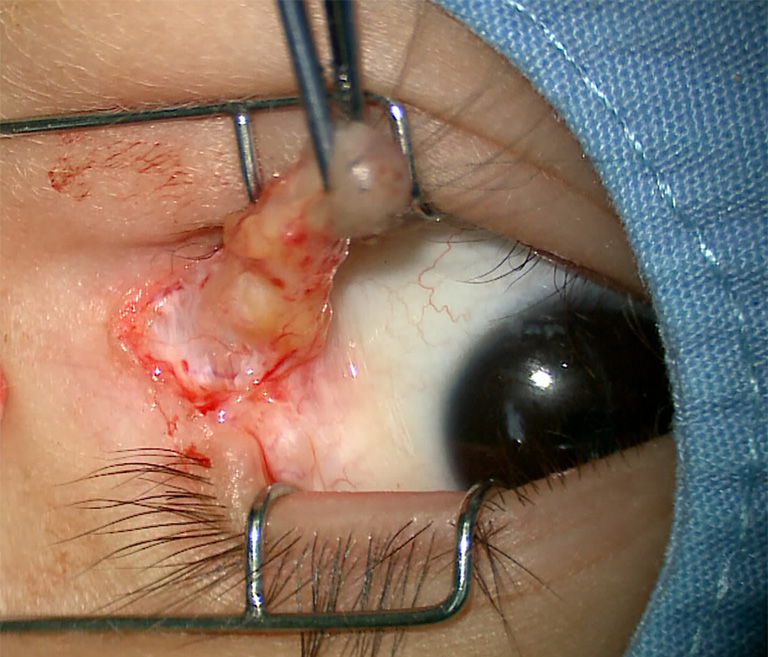

2例患儿均行全麻下眼睑肿物切除及眼睑成形术,术中探查见2例眼睑肿物均与颞侧球结膜粘连并延伸至外眦部眼球表面,基底部蒂较宽,眼球表面结膜肿物为淡黄色,质软,包膜薄,表面有毛发,与球结膜及筋膜相粘连(图3),外眦部部分睑缘缺损(图4)。沿肿物与皮肤延续的基底部切除皮肤肿物,同时切除结膜表面肿物,对睑缘凹陷及缺损部位进行对位修补及眼睑成形(图1、图2)。病理检查示:皮赘伴结膜皮样脂肪瘤,结节样肿物表面被覆鳞状上皮,皮下见皮肤附属器及分化成熟的纤维脂肪血管组织(图5),病例2局灶见钙化(图6)。

20221226171651_3664.png

图3 术中见肿物表面有毛发,基底部蒂宽,与颞侧球结膜及筋膜相粘连

Figure 3 Intraoperative photograph shows the mass has surface hairs and wide base, adhering to the temporal bulbar conjunctiva and fascia

20221226171718_7008.png

图4 术中切除肿物后见外眦部部分睑缘缺损

Figure 4 Lid coloboma at lateral canthus was observed after resection of the mass